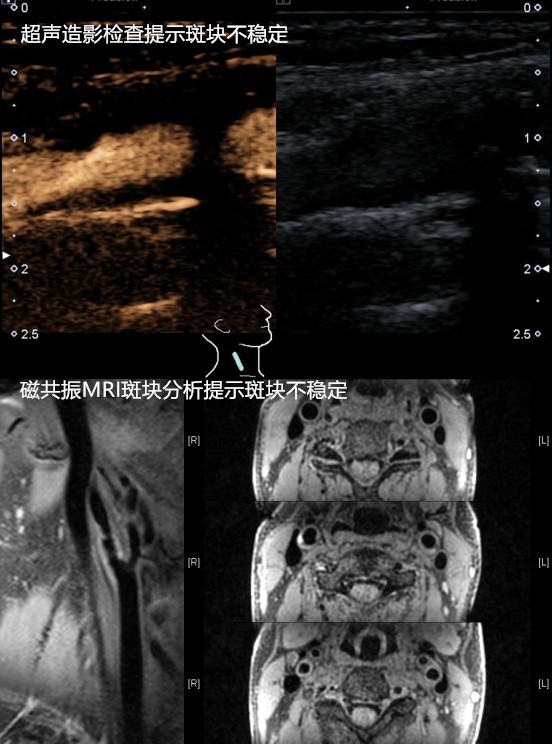

李伯伯今年61岁,吸烟40余年,发现高血压2余年,最高185/85mmHg,一直未规律服药。退休之后本想享享清福,没承想3个月来一直头晕乏力,偶尔还有眼前发黑视物不清。就诊清华长庚医院血管外科门诊,检查发现右侧颈动脉粥样硬化斑块形成、重度狭窄,超声造影检查及颈动脉斑块MRI分析均提示不稳定斑块,极易破碎脱落导致脑梗死。血管外科团队为李伯伯行颈动脉内膜剥脱术,术后症状明显缓解,恢复5天后顺利出院。

颈动脉彩超检查能够做出初步判断,但其受检查技师操作经验及主观判断影响大。为了进一步指导手术治疗,还需要明确颈动脉狭窄部位、长度以及程度、斑块成分等详细信息。颈动脉血管造影(DSA)能准确检查出动脉狭窄的程度和范围,是诊断动脉病变的金标准。近年来,应用超声造影技术、CT血管增强(CTA)以及磁共振血管成像(MRA)技术,同样可以得到全面的动脉狭窄信息,通过三维建模从不同的角度显示血管结构,良好地识别不稳定斑块。